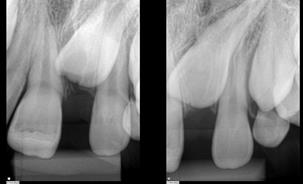

An 8-year-old male patient attended the Emergency Children's Dental Care at the Children's Specialties Clinic-Baby-Clinic of the State University of Londrina, for immediate treatment after a fracture in the right upper central incisor due to a fall during a school sports activity. On intraoral physical examination, a coronal fracture of the enamel and dentin was diagnosed without involvement of the pulp tissue (Figure 1). Response to the vertical and horizontal percussion test was not suggestive of endodontic and periodontal alterations, respectively, and impairment of the periodontal insertion was also ruled out through the mobility test in the buccal-palatal direction.On radiographic examination (Figure 2) confirmed the absence of periodontal and periapical involvement, as well as the absence of root fracture.